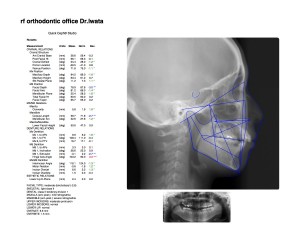

今の歯並びや噛み合わせがどうなっているのか、

顎の骨の形状や虫歯の有無を精密に調べるためにレントゲン撮影と写真撮影を行います。

そして、約2週間後に診断を受けました。

3Dシュミレーション画像や装置のサンプルを見せて頂きながら、私に最適な治療プラン•治療期間等の説明を聞きました。